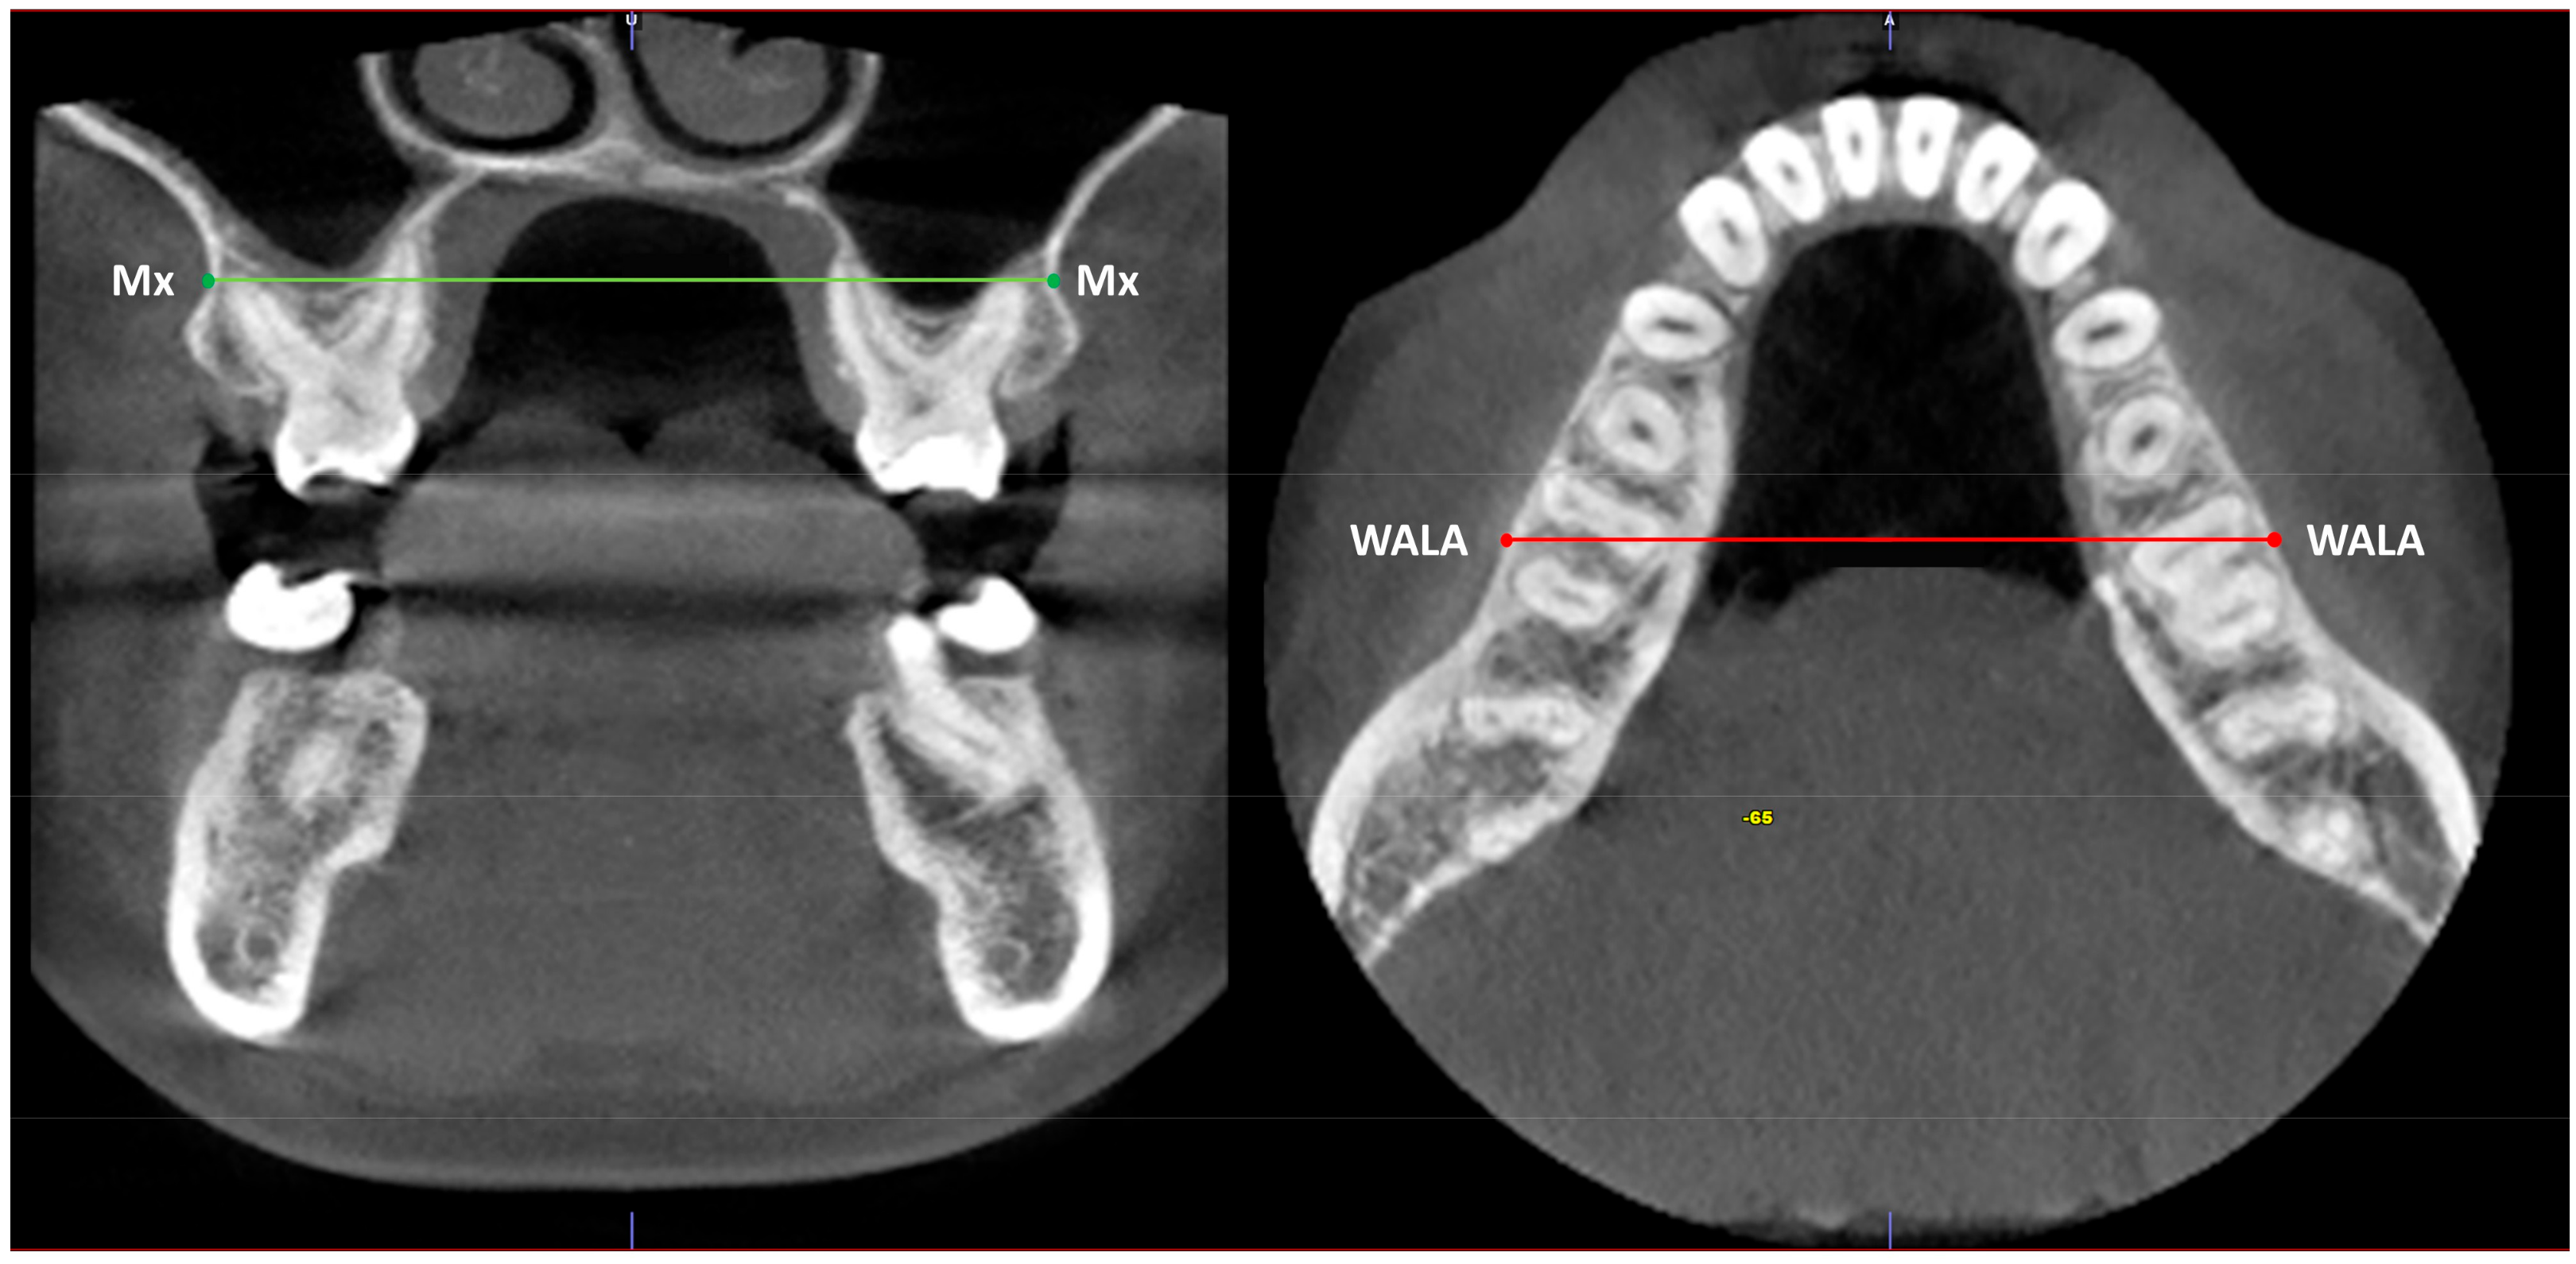

2. Materials and Methods